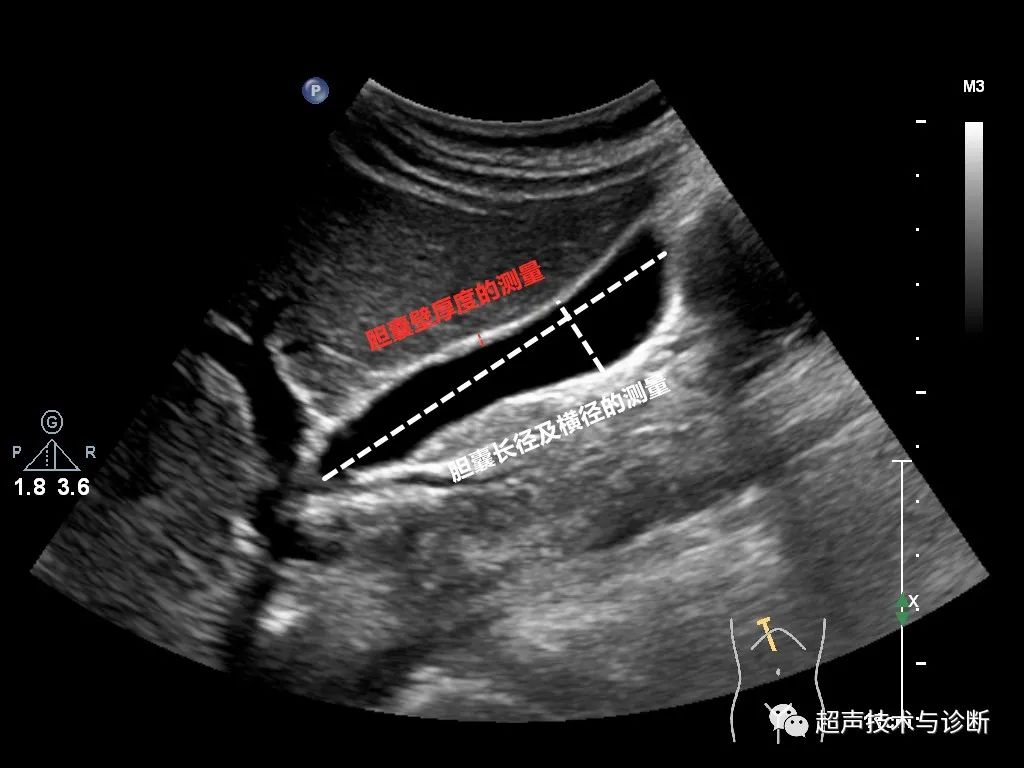

测量部位及方法:①胆囊长径:测胆囊颈部至胆囊底部内腔最大长径,如胆囊明显折叠,则分别测颈部至折叠、折叠至底部两段径线并相加。②胆囊横径:与胆囊长径垂直的径线。③胆囊壁厚度:于胆囊体底部前壁测量,尽量选择与声束垂直处测量最大厚度。